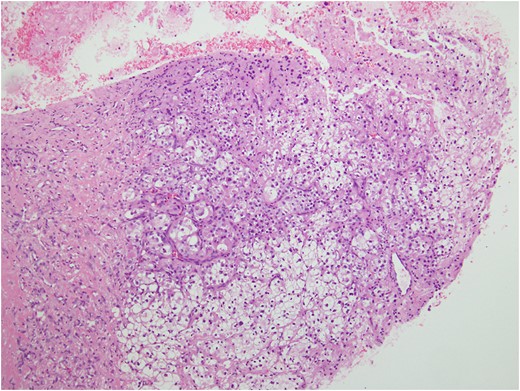

Histologic sections of the mass show distinct variably sized and shaped collections of uniform polygonal tumor cells, separated by fibrovascular septa and delicate capillary-sized vascular channels lined by flattened endothelium at low magnification (Fig. 5). Within the tumor nests, there is loss of cellular cohesion and necrosis of the centrally located cells in the nests results in the pseudo-alveolar pattern (Fig. 6). Vascular invasion is also present (Fig. 7). The individual tumor cells have distinct cell borders and abundant eosinophilic to clear, somewhat granular cytoplasm surrounding a central nucleus with variably sized nucleolus. Nuclear atypia is rarely seen. Mitotic figures are uncommon. The cells contain rhomboid or rod-shaped crystalline inclusions that are faintly apparent on routine histology and are better demonstrated with periodic acid-Schiff stain after diastase digestion (Fig. 8).

Loss of cellular cohesion and necrosis of the centrally located cells in the nests.